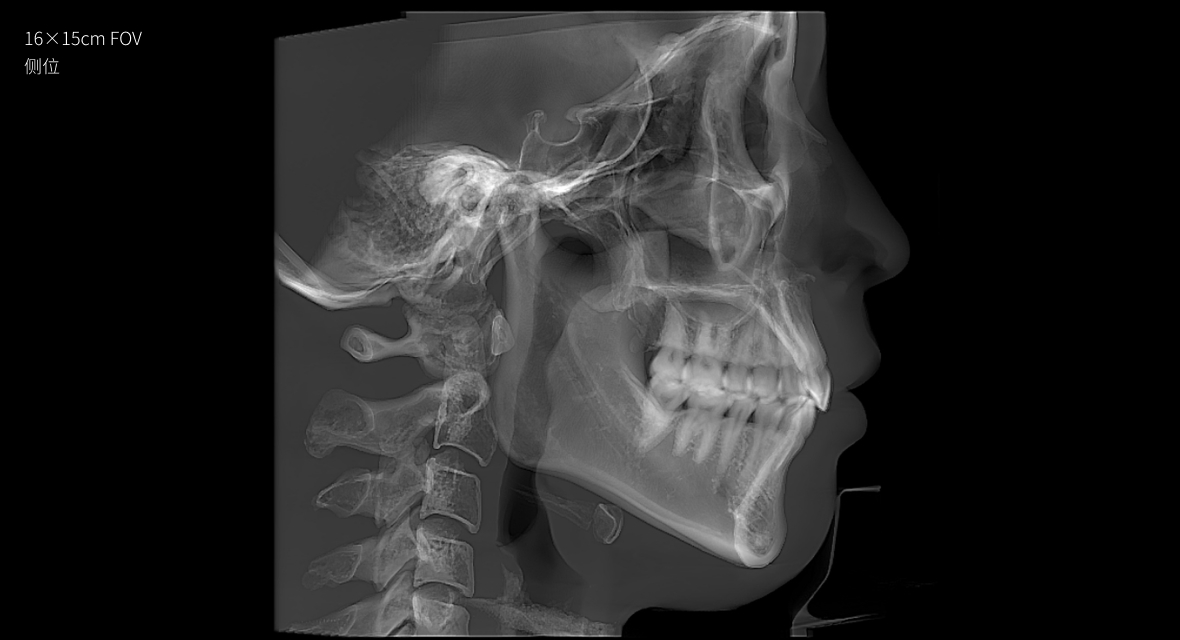

• 3D 正側位

3D 正側位

16×15cm

非拼接大視野